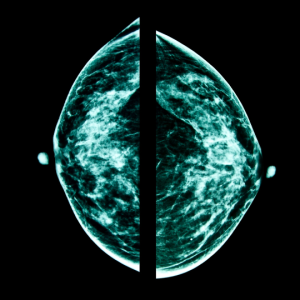

Mammography

Mammography is a specialized medical imaging technique used to screen for and detect breast cancer in its early stages. It involves taking low-dose X-ray images, called mammograms, of the breast tissue to visualize any abnormalities, such as tumors or calcifications.